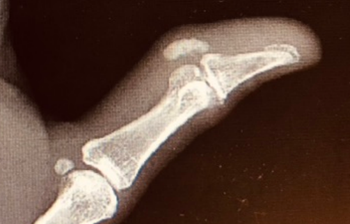

Our latest case report from Brady Pregerson, MD, featuresa woman in her mid-60s with a history of Hashimoto’s thyroiditis treated with levothyroxine presenting to the hospital with 4-5 days of pain, swelling and redness on her left thumb.